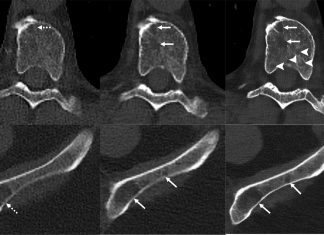

Scientists Develop an Improved Method for Detecting Myeloma Bone Disease using...

Scientists have developed a new CT technique using artificial intelligence (AI) to spot multiple myeloma-related bone diseases, using lower radiation doses than conventional CT,...